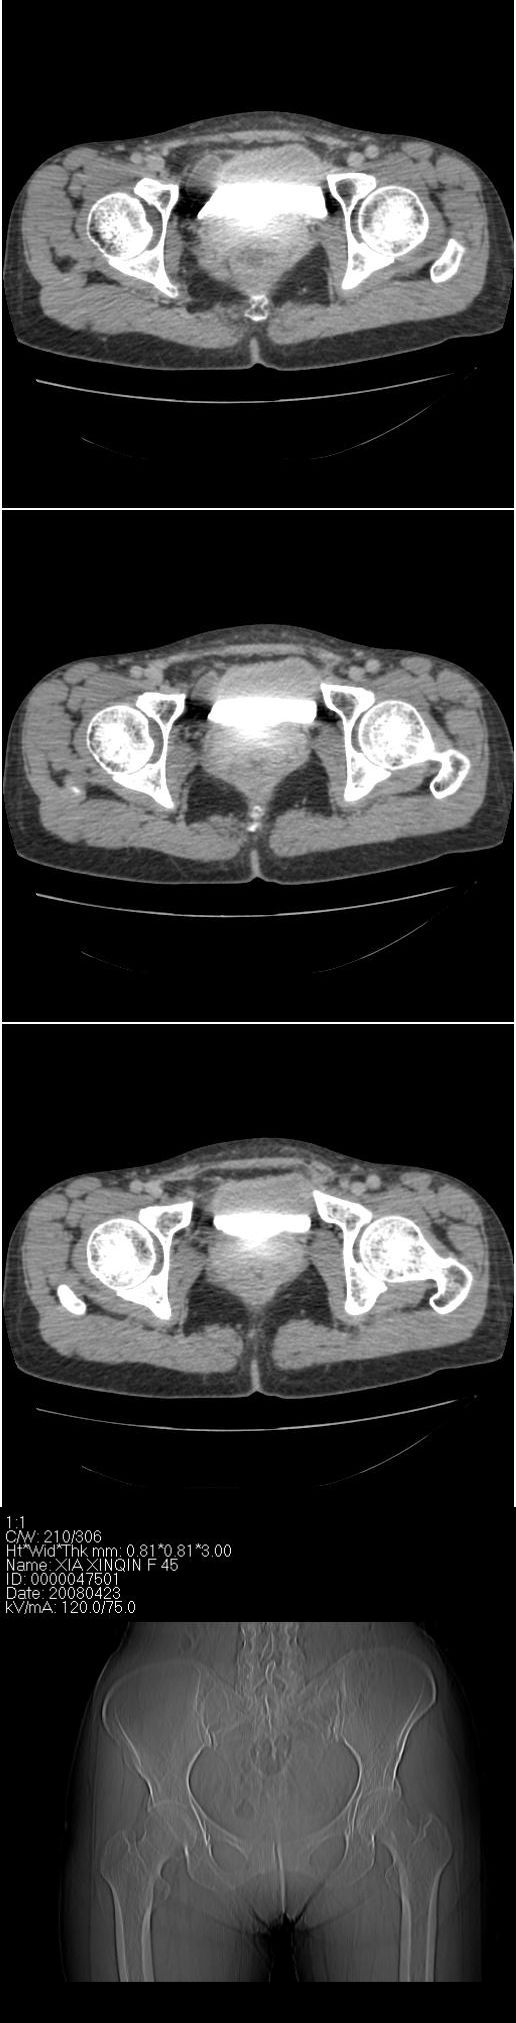

该病人今天做了增强,右侧髂骨病灶明显强化。

右侧髂后上棘局限性囊状骨质破坏,大部分界清,似见轻度硬化边,内无分格及钙化,病灶上部局部显示模糊。考虑;骨巨细胞瘤可能大,不除外abc。另可见子宫肌瘤术后子宫缺如。

临床和影像学表现:女性患者46岁,有子宫肌瘤手术病史。影像所见可见残余宫颈部分,左右附件未见新生物;右髂骨翼后端囊状膨胀性骨破坏,囊性部分感觉有强化(楼主标上增强前后的ct值就很好了),未见明确的液—液平面,周边硬化不明显或轻度硬化。

分析:患者年龄46岁,没有明确外伤病史,病变呈膨胀性骨破坏,囊性部分未见明确的液—液平面,周边硬化不明显。综合分析该病例比较符合骨巨细胞瘤,不太符合动脉瘤样骨囊肿。

诊断:1、首先考虑骨巨细胞瘤;2子宫肌瘤术后改变